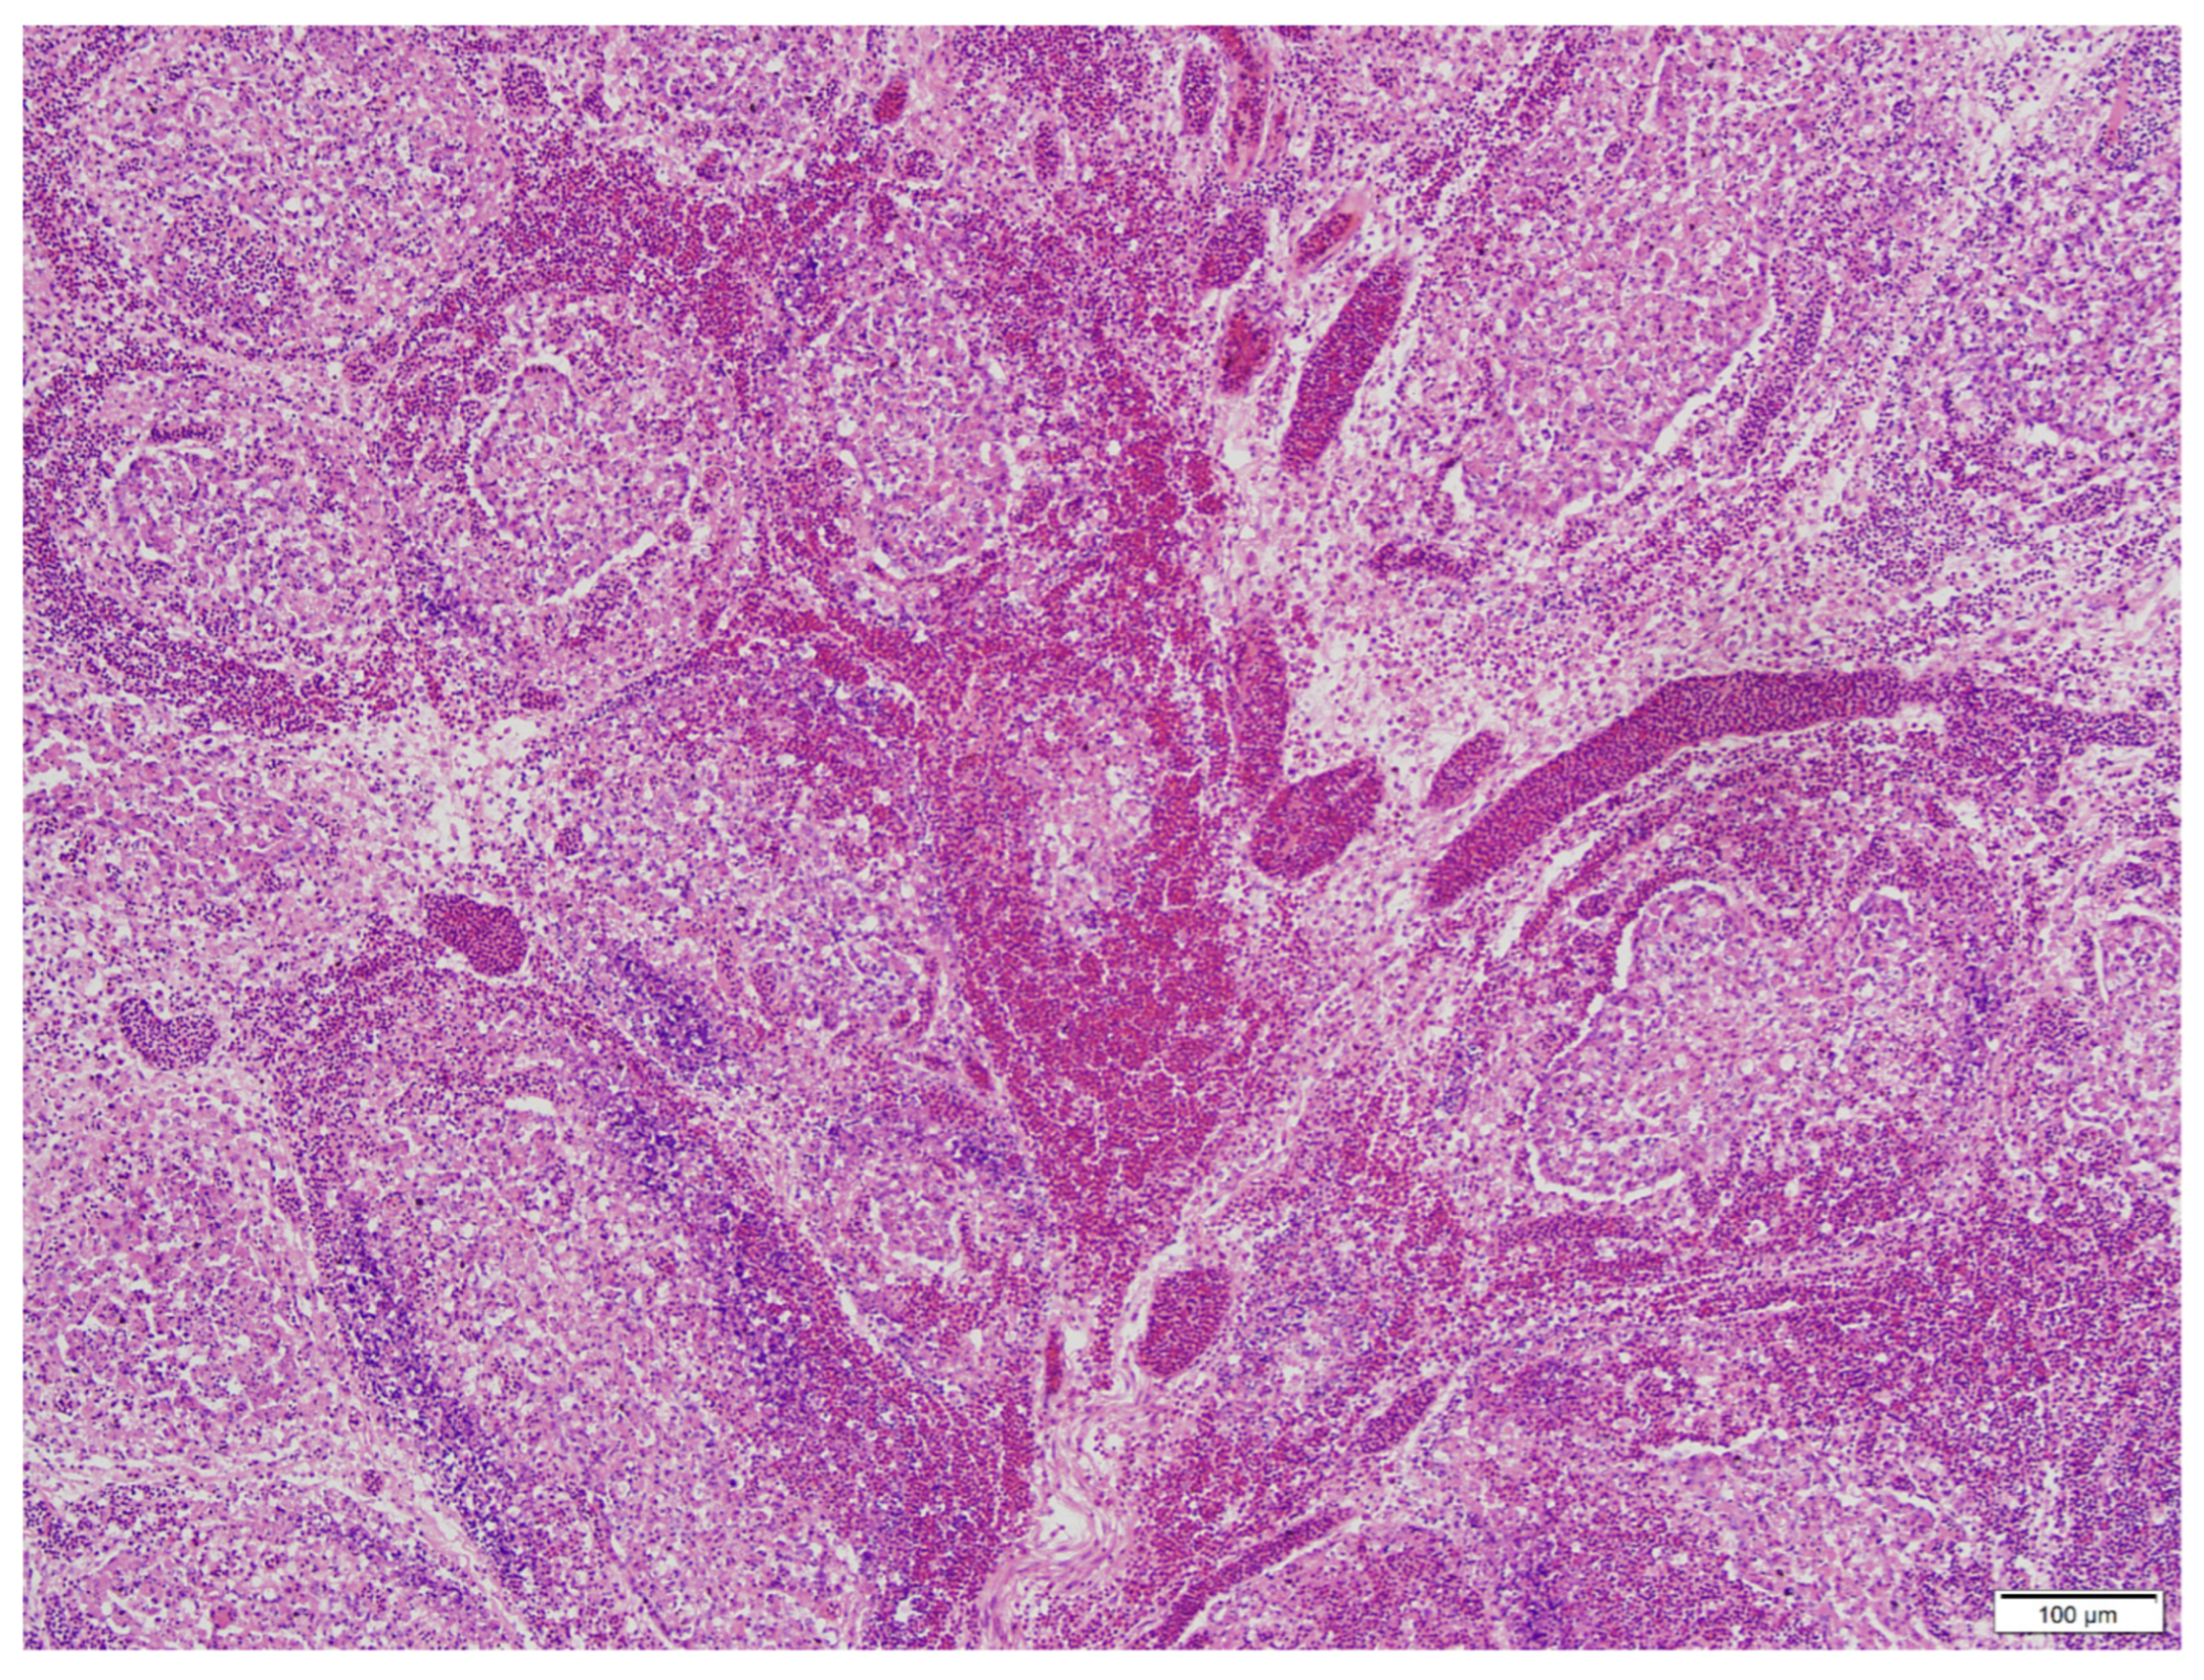

3.2. Histopathology